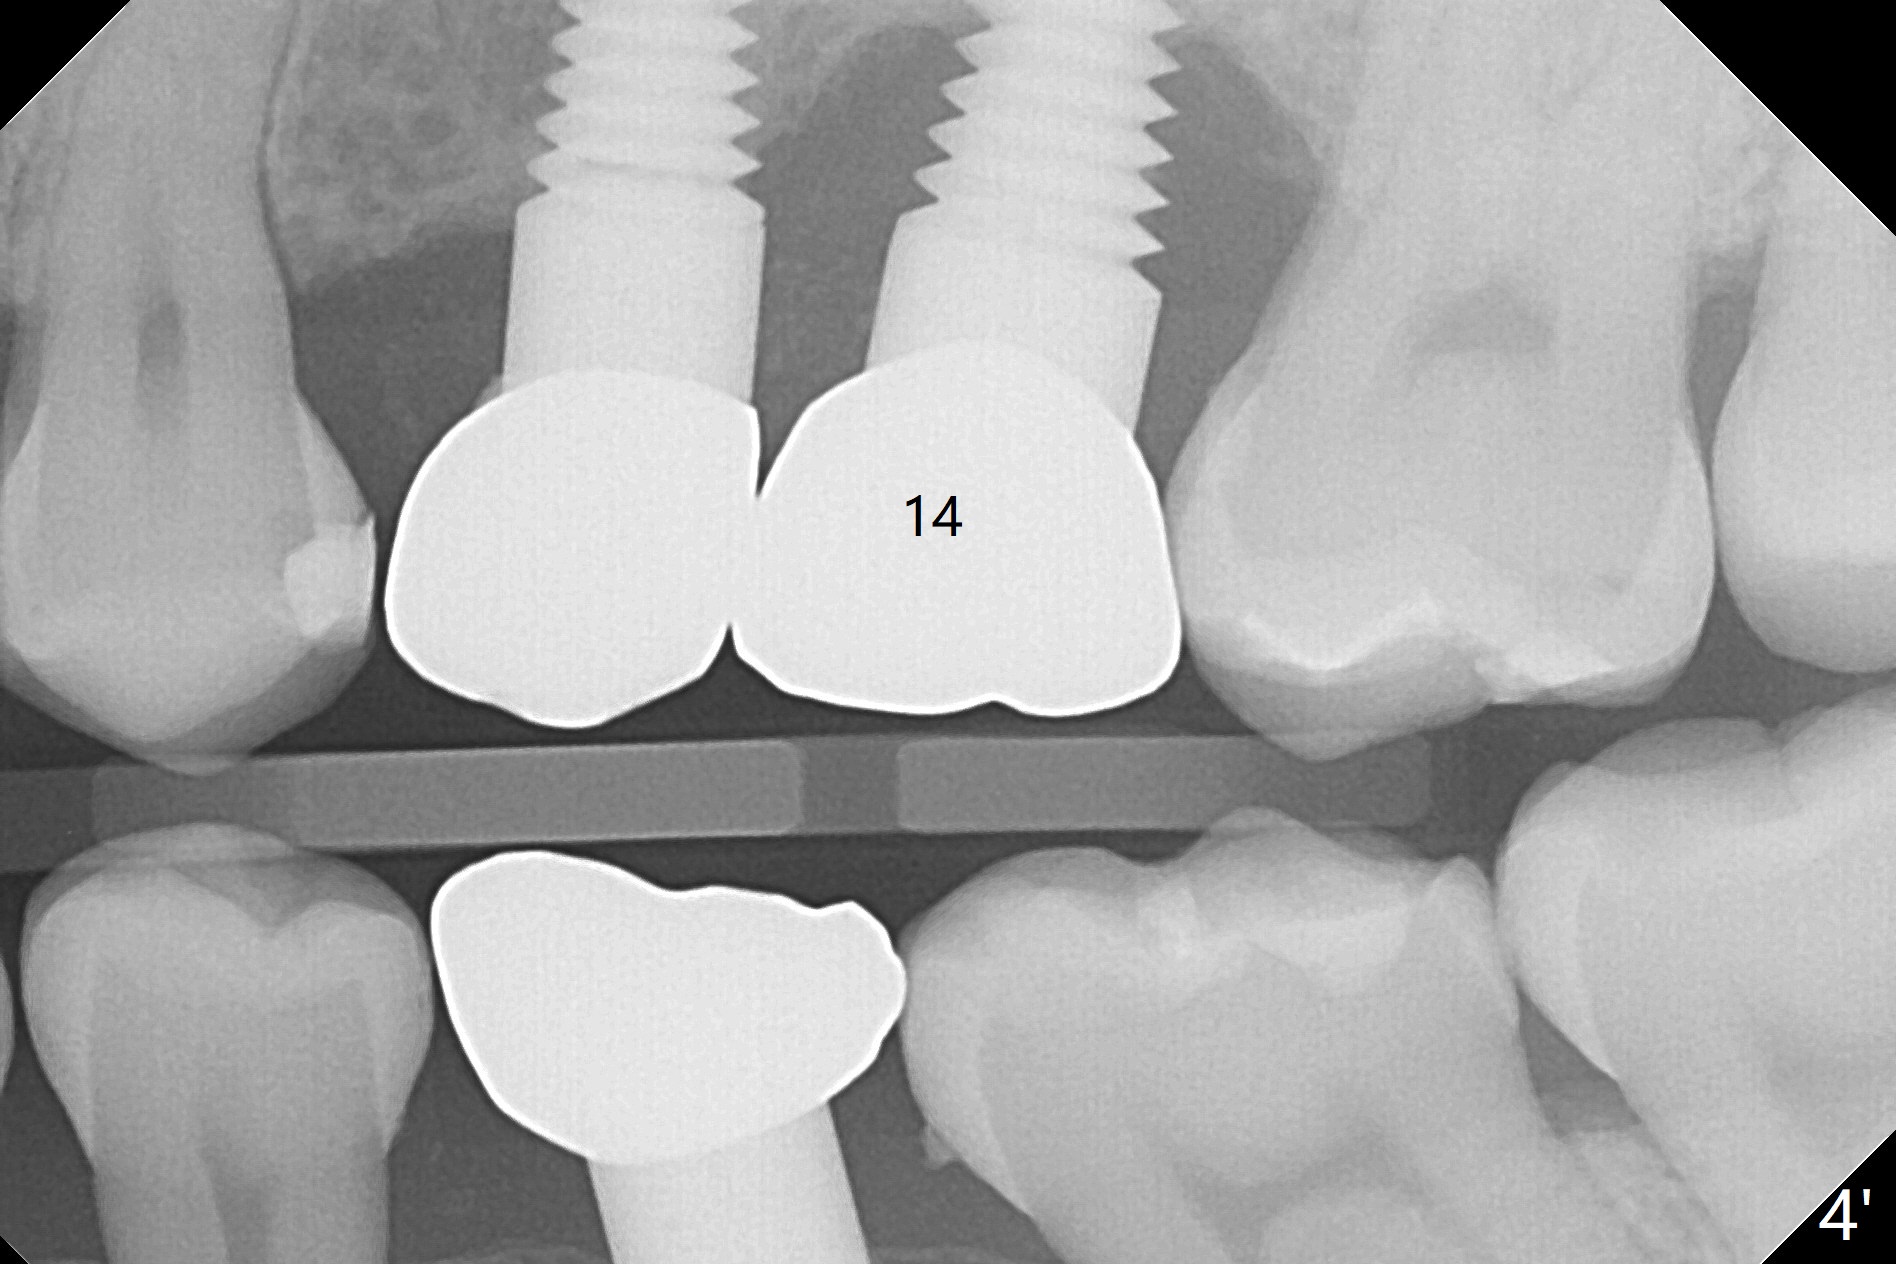

A 32-year-old woman develops periimplantitis (severe hemorrhage and deep pockets) at #14 three years 7 months post cementation (Fig.1).  A 4.5x11 mm implant is placed with flap at #13 after failure for the 1st time (Fig.2), while a 5x11 mm implant is placed flapless with sinus membrane perforation.  Uniposts are cemented with Ketac.  The lingual plate at #14 is defective (Fig.3).  The implant at #14 will be removed flapless, followed by Osteogen plug (most likely sinus floor defect) and bone graft.  After healing, an implant will be placed with guide.  By breaking the proximal contacts, the crown, abutment and implant at #14 are shaken loose using forceps.  Finally the crown breaks off.  Make a slot on the top of the abutment and use a screw bit to turn the abutment/implant counterclockwise.  There is abundant granulation tissue with arterial hemorrhage associated with granulation tissue removal.  The defect involves the distal surface of the implant at #13 and the mesial surface of the tooth #15.  Therefore bone graft is deposited in these surfaces (Fig.4 arrowheads, as compared to preop BW, Fig.4').  The periodontal dressing seems to remain in place asymptomatic 7 days postop (Fig.5).  The bone height 5.5 months postop should be enough for implantation (Fig.6).  To avoid marker associated with guided surgery, free hand will be adopted.  Sinus lift with PRF is expected.  To place in the middle of the ridge buccopalatally, incision will be made with bone expansion.